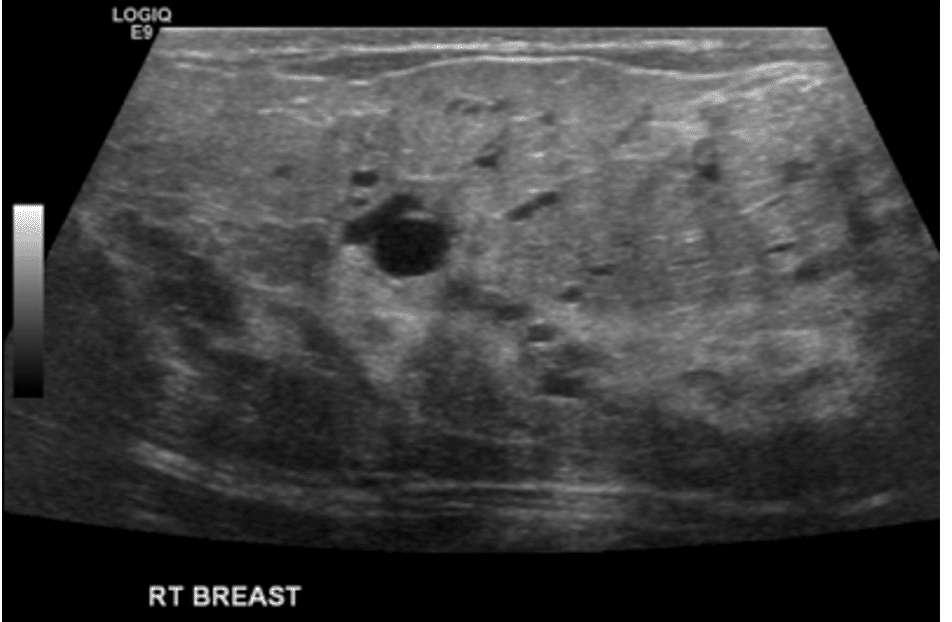

Phlegmon

A phlegmon is an indistinct area of tissue inflammation, fluid collection, and inflamed capillaries (blood vessels). It can present with redness overlying the area of massage or it can present with a mass-like area in the breast. Ultrasound should confirm the difference between a phlegmon and an abscess (which is a fluid collection that requires drainage).

Phlegmon are managed with the same principles as plugging and mastitis. They may or may not coalesce into an abscess (drainable fluid). Abscesses will eventually drain spontaneously through the skin or obstruct the nipple region if they are not treated appropriately.